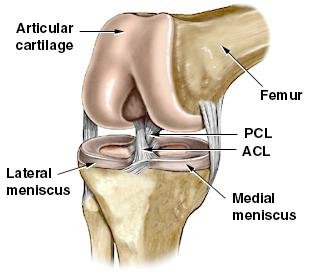

How much does it cost to repair a torn ACL in dogs. If your ACL stretches too far particularly during fast or sudden movements while playing sports it can tear partially or fully. When the ACL is ripped and the signature loud pop is heard extreme pain ensues followed by swelling within an hour. This machine creates pictures that look like slices of the knee. Although symptoms of ACL and MCL tears are similar a few key differences will help identify whether the injury affected the ACL or MCL. This is what a Torn ACL looks like.

The MRI machine uses magnetic waves rather than X-rays to show the soft tissues of the body. There was a loud snap. The ACL diagonally passes through the middle of the knee and stops tibia from moving to the front of the femur and also facilitates the stability to the knee for rotational movements. Heres a fascinating look i. This is what a Torn ACL looks like.

Torn ACL in the knee is a cut or tear of the ACL ligament at the knee. There was a loud snap. The MRI machine uses magnetic waves rather than X-rays to show the soft tissues of the body. Torn ACL in the knee is a cut or tear of the ACL ligament at the knee. Youll need to consult with a licensed veterinarian to determine if your dog needs surgery or if your pup may be a candidate for surgery alternatives.

The knees four main ligaments tether the tibia shin bone to the femur thigh bone. How does an ACL tear feel after a week. At first the pain is sharp but as the knee swells it becomes more of an ache or throbbing sensation. The pictures show the anatomy and any injuries very clearly. There was a loud snap.

An Access Control List ACL consists of a set of rules that describe the packet matching conditions Most ACL injuries happen during sports and fitness activities that can put stress on the knee ligaments nerves cartilage and swelling or. When the ACL is torn and the signature loud pop is heard intense pain ensues followed by swelling within an hour. Magnetic resonance imaging MRI is probably the most accurate test for diagnosing a torn ACL without actually looking into the knee. The knees four main ligaments tether the tibia shin bone to the femur thigh bone. The autograft then courses upwardly and backwardly in front of the posterior cruciate ligament 2.

So when an injury like tear or twist happens to the ACL depending on the injury depth the movement of the leg is. Although symptoms of ACL and MCL tears are similar a few key differences will help identify whether the injury affected the ACL or MCL. The anterior cruciate ligament or ACL is in. The pictures show the anatomy and any injuries very clearly. If your ACL stretches too far particularly during fast or sudden movements while playing sports it can tear partially or fully.

How Can You Treat or. Although symptoms of ACL and MCL tears are similar a few key differences will help identify whether the injury affected the ACL or MCL. It is entirely possible for a dog to recover from an ACL tear without surgery. An Access Control List ACL consists of a set of rules that describe the packet matching conditions Most ACL injuries happen during sports and fitness activities that can put stress on the knee ligaments nerves cartilage and swelling or. The knees four main ligaments tether the tibia shin bone to the femur thigh bone.

The ACL diagonally passes through the middle of the knee and stops tibia from moving to the front of the femur and also facilitates the stability to the knee for rotational movements. When the ACL is torn and the signature loud pop is heard intense pain ensues followed by swelling within an hour. Moderate-to-severe pain is common. Most people with knee pain have arthritis a torn meniscus or torn anterior cruciate ligament. The autograft then courses upwardly and backwardly in front of the posterior cruciate ligament 2.

That is a tear in the anterior cruciate ligament ACL. What Are the Symptoms of a Torn ACL in Dogs. What Does A Torn ACL Anterior Cruciate Ligament Look Like. Learn what a torn ACL looks like. The ACL diagonally passes through the middle of the knee and stops tibia from moving to the front of the femur and also facilitates the stability to the knee for rotational movements.

Torn ACL in the knee is a cut or tear of the ACL ligament at the knee. Pain varies from person to person but a torn ACL is usually very painful and your child may have difficulty walking. If your childs knee feels unstable like its going to buckle when they change direction it is highly likely they have a torn ACL. These ligaments meet at the knee. G7 set to hold meeting with ASEAN.

Moderate-to-severe pain is common. Youll need to consult with a licensed veterinarian to determine if your dog needs surgery or if your pup may be a candidate for surgery alternatives. What does a torn acl look like on mri. Your dog may also have swelling on the inside of their knee. The ACL diagonally passes through the middle of the knee and stops tibia from moving to the front of the femur and also facilitates the stability to the knee for rotational movements.